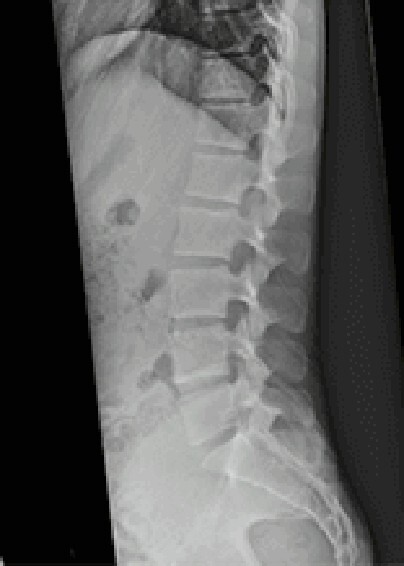

MRIとは

MRI装置は、磁力を使って体の様々な断面像を撮像しますので、放射線による被曝はありません。 また、頭部、四肢関節、脊椎、腹部、他全身の画像を撮像したり、造影剤を使用せずに血管・膵管・胆管等の情報を得ることもでき、全身の診断に大変効果があります。